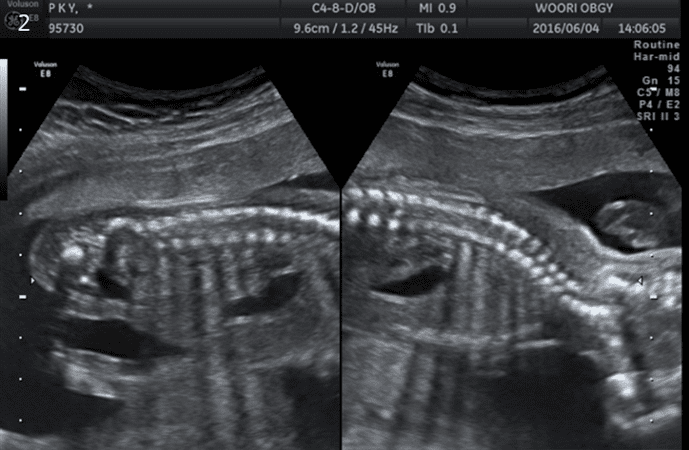

4D 입체영상초음파

입체영상초음파는 선택검사이며, 예약이 필요합니다. 태아의 얼굴, 손, 발, 척추 등이 가장 잘 보이는 임신 23-28주 사이에 실시하여 실물과 유사한 사진을 얻어 미리 아가를 만나볼 수 있는 검사입니다. 우리산부인과는 보다 감각 있는 사진을 위하여 초음파 "GE HD live "을 사용하고 있습니다.